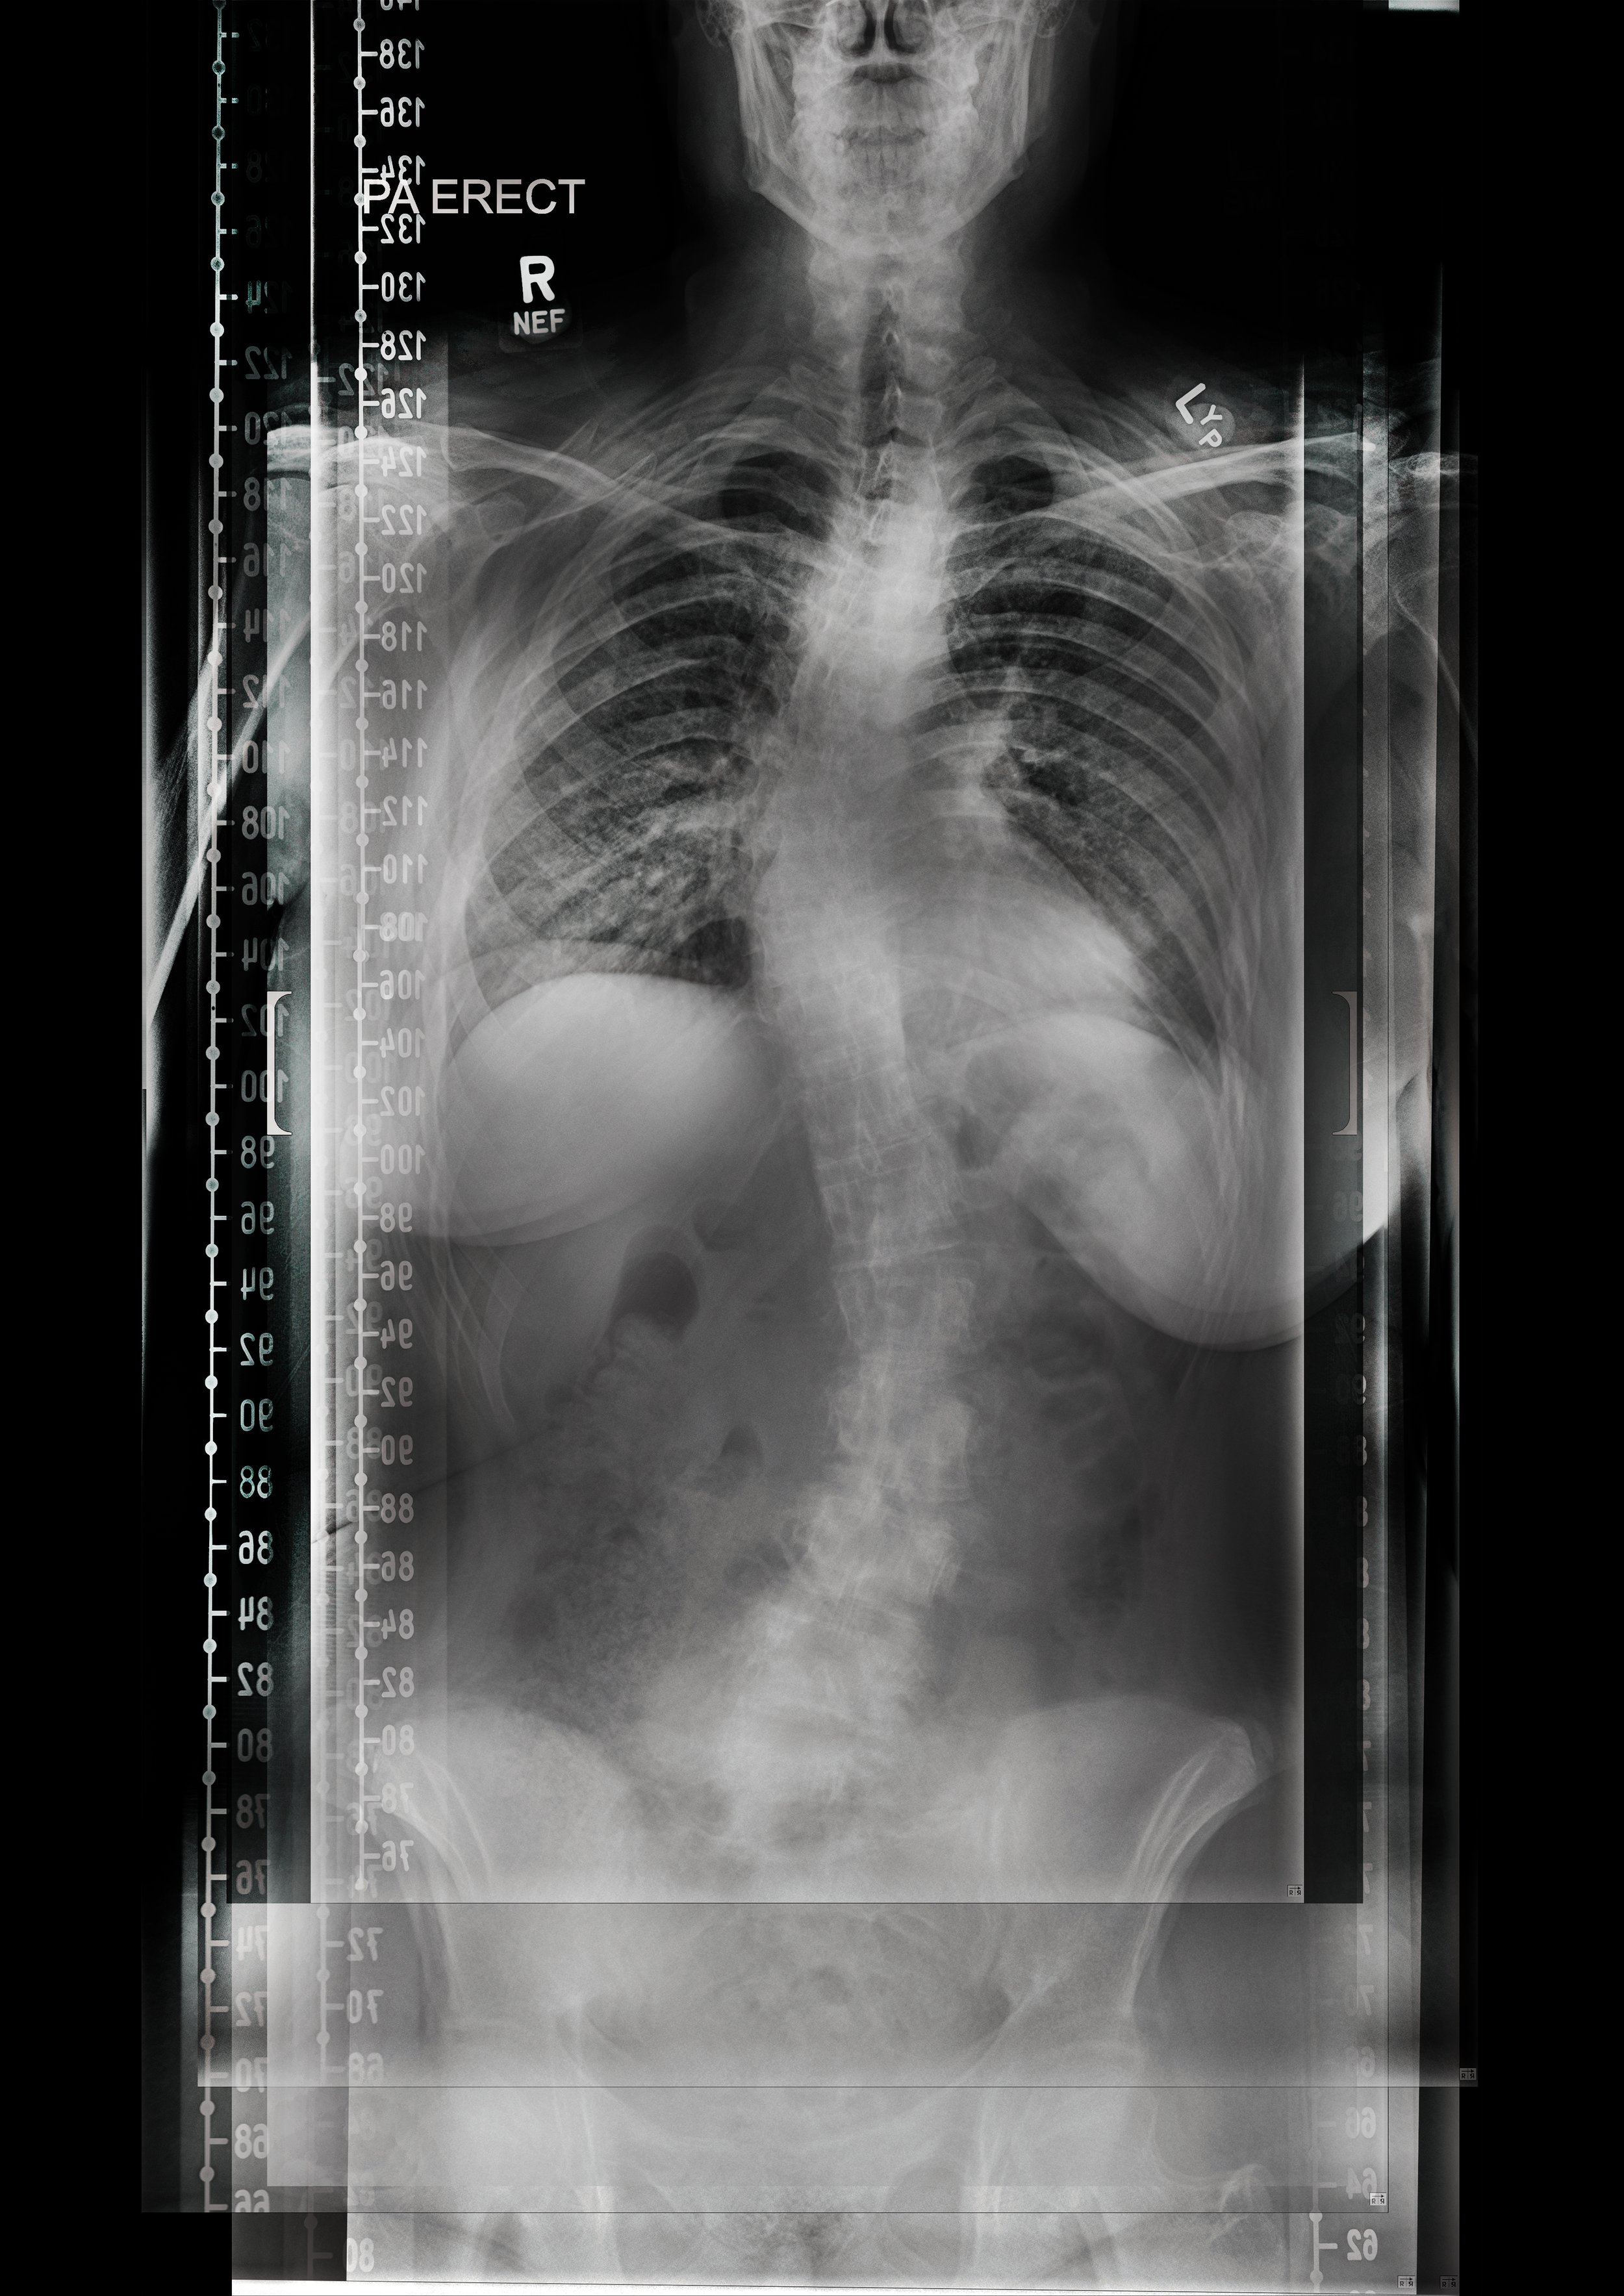

Defining Practice - 3D Scoliosis Spine